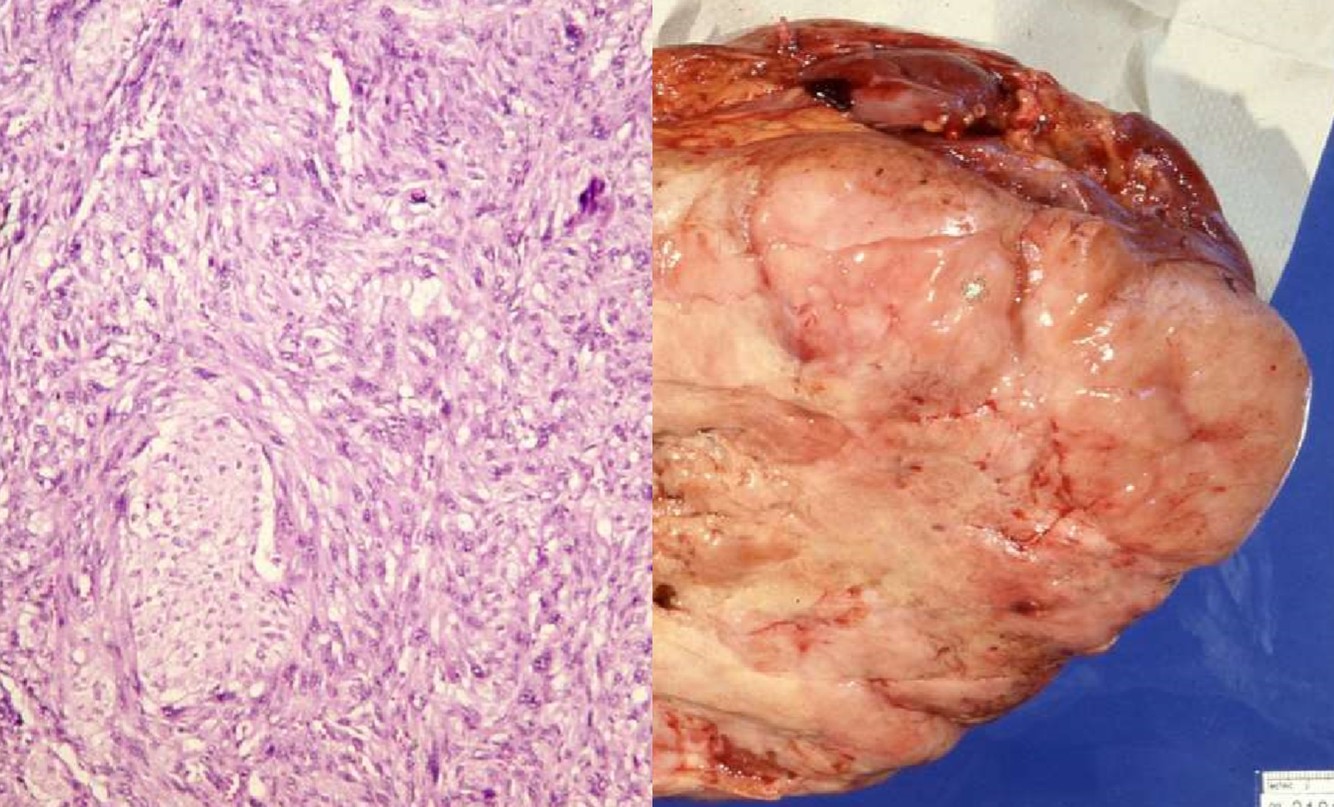

XANTHOGRANULOMATOUS PYELONEPHRITIS

- Often associated with large staghorn calculi of renal pelvis

- Many of these patients may have UTI, secondary to E. coli or Proteus

- May presents as a mass-like lesion